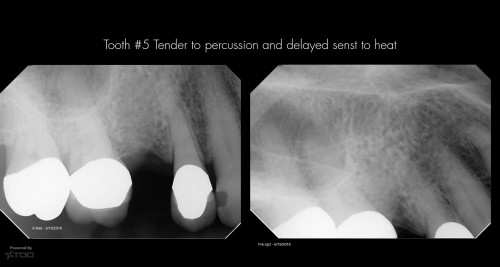

Dual Entry Access

66 yof. SIP following crown preparation and removal of caries. The permanent crown is ready […]